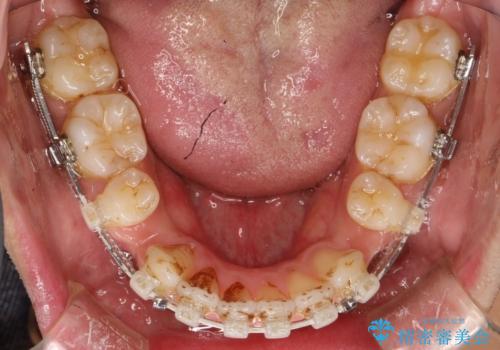

前歯の隙間を閉じたい 口元も下げたい ハーフリンガルによる抜歯矯正

- 矯正装置

- ハーフリンガル

上下左右の歯を1本ずつ抜歯しして、上顎の前歯を後方に移動させるのと、正中の隙間を閉じる計画としました。

装置はなるべく目立たないものをご希望でしたので、ハーフリンガルを選択されました。